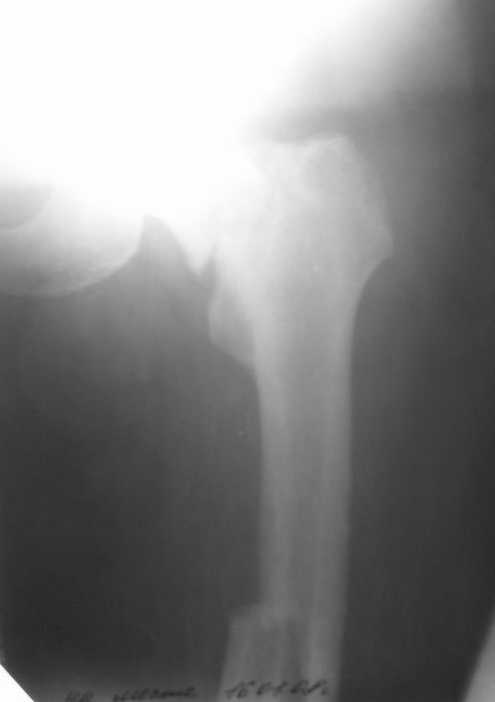

Лечился в ЦРБ. К нам поступил вчера. Имеется оскольчатый перелом диафиза левого бедра, перелом медиального мыщелка, краевой перелом надколенника. У нас, кроме того, выявили перелом шейки бедра. Перелом закрытый, имеется рана в в/3 голени(ниже уровня бугристости б/берцовой кости)без признаков инфицирования.Планируем закрыто фиксировать мыщелок и надколенник винтами, затем закрыто заштифтовать бедро. Вопрос возник по перелому шейки: что предпочесть - длинный PFN или DFN + DHS на шейку?Буду благодарен за ценные советы.С уважением, Станислав Дмитриев.

Заранее приношу извинения за качество снимков. То что есть - либо из ЦРБ, либо сделано в приемном покое, где дежурят рентгенлаборанты различной квалификации. Завтра постараемся сделать снимки всего бедра на длинные кассеты в 2 проекциях. Сейчас больной на скелетном вытяжении. Состояние стабильное.

Я тоже склоняюсь к такой версии.Перелом практически базальный, тип Пауэлс 3 - однозначно нужна угловая стабильность - ни о каких спонгиозных винтах речи нет. Возраст 46 лет, т.е. достаточно молодой - насчет ас. некроза. Накладку DHS вероятно придется ставить монокортикально - штифт получается до малого вертела. Померили расположение имплантов - что называется "стык в стык".

Насчет PFN. Заблокировать проксимальный отломок диафиза будет проблематично.Как репонировать шейку при неблокированном верхнем диафизарном фрагменте? У PFN проксимальный блокирующий диафизарный винт при введении "конфликтует" с нижним шеечным винтом. Фиксация шейки на одном верхнем винте,на мой взгляд, недостаточна. Затем, помню высказывания на форуме Джолдаса Кульджанова на счет ипсилатеральных переломов, о том что "лечить" их надо "по отдельности".Там же были картинки со сломанными шеечными винтами PFN. К сожалению ссылку дать не могу.